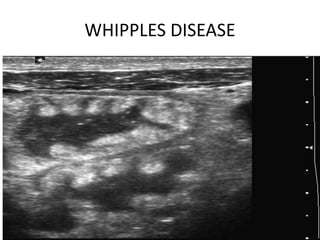

WHIPPLES DISEASE